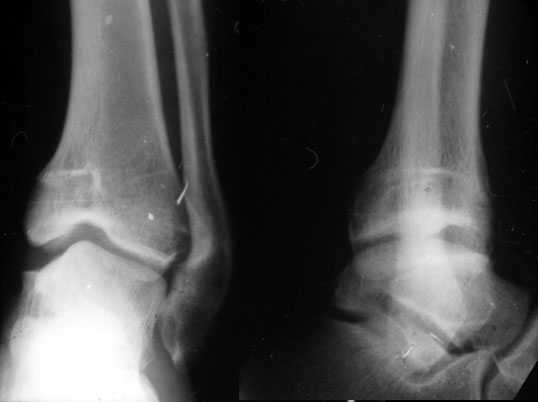

Аппаратом можно сделать все минимально инвазивно и травматично, вырастить клиновидный регенерат после чрескожной остеотомии через один или два разреза 0,5 см. В приложении похожий по локализации случай, только более давние последствия травмы с замыканием части зоны роста, деформация побольше, плюс укорочение голени было.